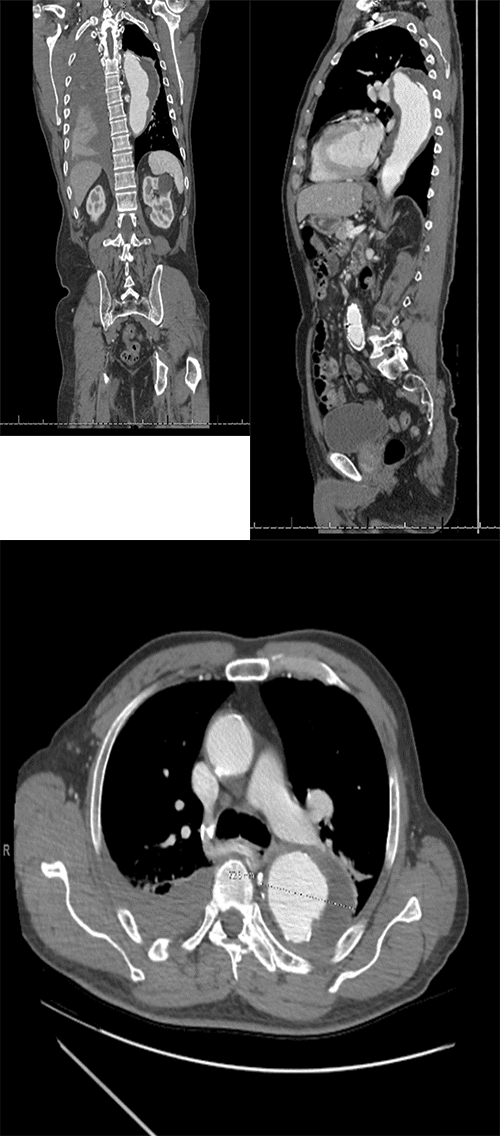

• Thoracic aortic aneurysm (TAA) involving zones 1-5, measuring 7.3 cm in diameter and containing intramural thrombus (Figure 1)

Figure 1. CT Scan Images. Published with Permission

(Left to right) A large descending thoracic aortic aneurysm measuring up to 7.5 cm in diameter with a 2.5 cm thrombus on the left lateral aspect. Additionally, there are non-displaced fractures of the right clavicle and ribs 2-6 with associated hemothorax on the right side